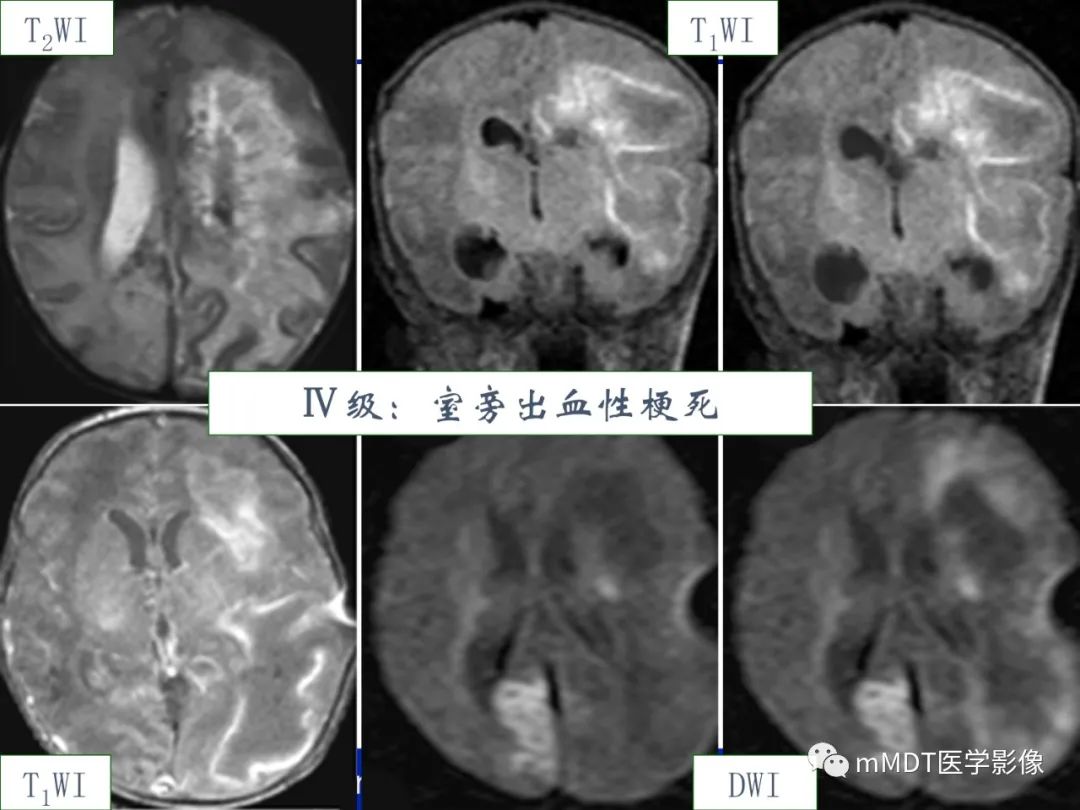

HIE的分度

Ø脑损伤的部位—-脑室周围为主ØØ脑损伤类型、发病机制:

l胚胎生发基质-脑室内出血(germinalmatrix hemorrhage and intraventricular hemorrhages,GMH-IVH)、小脑出血,生发基质未完全退缩、毛细血管的血管壁不成熟,易发生出血;

l脑室旁白质软化(periventricularleukomalacia,PVL),血管的终末段(胎龄越小,髓质穿通动脉发育越差,分支少),缺血易发生白质的坏死。